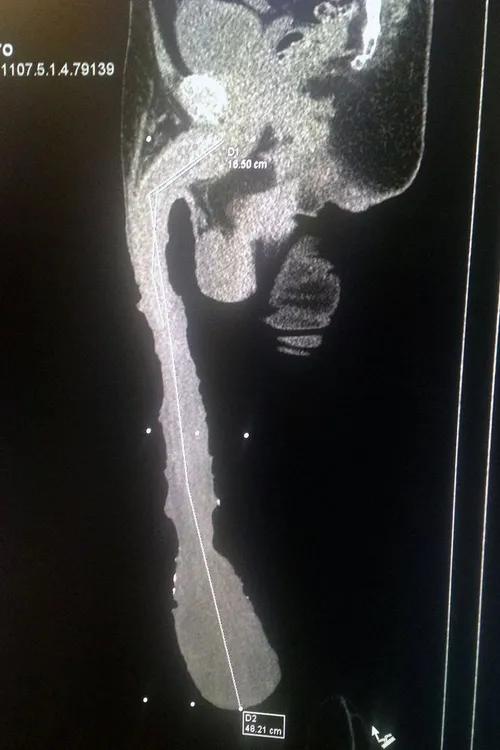

Je zal ‘m maar in je broek hebben hangen, de grootste penis ter wereld. Roberto Esquivel Cabrera is de trotse eigenaar van deze unit van een tampeloeres. Zijn piemel heeft in slappe toestand een lengte van 46 centimeter. Yep, dat is wat je noemt een derde been.

Onlangs heeft de Mexicaan nog een operatie tot penisverkleining geweigerd, ondanks dat hij met zijn enorme apparaat geen seksleven heeft. ‘I am happy with my penis, I know nobody has the size I have. I would like to be in the Guinness Book of Records but they don't recognise this record,’ aldus de fors geschapen Zuid-Amerikaan.

Zijn piemel, die meer weg heeft van een babyolifantenslurf dan van een geslachtsorgaan, heeft en eigen sleeve en ingepakt waarmee die tot net onder zijn knieën komt. Dokter Jesus David Salazar Gonzalez adviseerde de man eerder al een penisverkleining te ondergaan, maar Roberto weigerde. ‘'Mr Roberto, the best thing for you is that the doctors give a normal shape to your penis so that it doesn't hurt you, in order to have sexual relationships, in order to have children. But he doesn't accept it, he'd rather have a penis bigger than the rest of the people.’

Daarnaast loopt ‘ie ook nog gezondheidrisico’s. Door de enorme voorhuid kan niet alle urine ontsnappen en heeft ‘ie veel kans op infecties. Met alle pus en ellende van dien. Verder moet z’n derde been tijdens het slapen altijd op een kussen liggen, omdat het anders te veel pijn gaat doen.